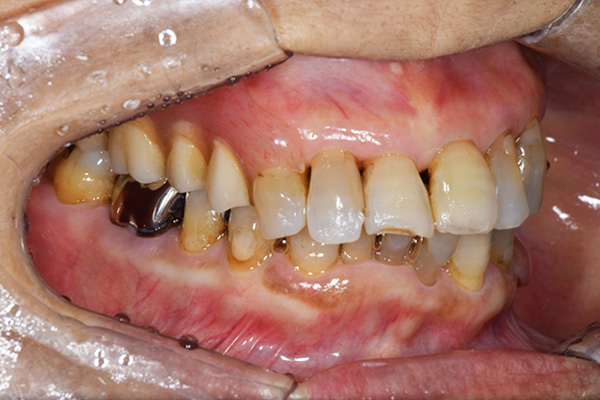

前歯が折れて当院にいらっしゃいました。 過去に下の入れ歯を作ったが、合わなくなってずっと入れ歯をいれていらっしゃらない患者様でした。 これは奥歯で噛むことができないため、前歯で噛むことを繰り返したために、負担に耐えられなくなった前歯が折れてかぶせ物ごと 外れてしまったのだと考えられます。 痛くない、違和感の少ない、下の入れ歯を作ることがこの方のゴールであると考えられました。

上下の入れ歯が外れやすくなったということでいらっしゃいました。 顎の骨はしっかりしていましたので、精密な型取りさえすればしっかりした入れ歯がつくれると思いました。 また下には6本歯が残っていましたが、虫歯になっている歯もありました。 かぶせ物のなかで大きな虫歯があった歯があり、1本だけ残せない状態でした。

上の入れ歯は確かに吸着は甘くなっていました。 また下の入れ歯はバネの一部が壊れており、安定感がなくなっていました。

右上と左下の歯がない方です。 上の入れ歯の安定が悪く、作り直したいとのことでいらっしゃいました。 今お使いの上の入れ歯を見てみると、口蓋部分が抜けており、安定性に欠ける構造になっていました。この入れ歯はノンメタルクラスプデンチャーといって、金属のバネを使用しない 入れ歯になります。これは見た目は良いのですが、歯への負担が大きいことと、入れ歯自体がやわらかいため、噛むには不便なことがあります。

右上のインプラント周囲炎で、その部分が痛いという患者様でした。 また奥歯で噛むことが難しかったため、前歯を使用することが多くなり、 前歯が前よりも前に出てきていることも気になっていらっしゃいました。

インプラント部以外にも歯周病が進行していましたので、歯周病の治療を行いました。 残念ながらインプラントと、1本の歯が残せなかったため抜歯を行いました。 その後、前歯の出っ張りを修正することと入れ歯の安定を図るため、残っている歯を全てかぶせ物にしていくことになりました。 写真中央は抜歯後に入れた治療用の入れ歯になります。 抜歯後歯ぐきが安定しましたら、入れ歯とかぶせ物の型取りを行いました。